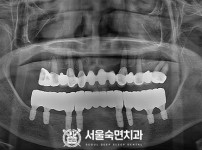

임플란트-전후사진4

치과를-선택할-때-꼭-확인하세요-서울숙면치과-임플란트-전후사진